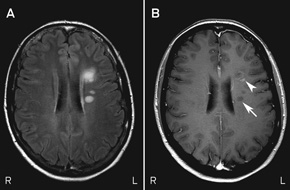

MRI scans of Mary’s brain and orbits showed altered signal intensity within the retrobulbar portion of the right optic nerve. They also showed six small areas of altered signal intensity in the supratentorial white matter affecting the periventricular and subcortical regions, one of which exhibited enhancement with the contrast agent gadolinium (Box 5). The simultaneous presence of enhancing and non-enhancing brain lesions (ie, actively inflamed and older lesions) is sufficient information to prove dissemination in time, and Mary could be told that she has MS without waiting for a second attack.